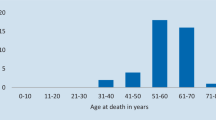

Follow-up

The mean duration of follow-up after dementia onset was 3.5 ± 2.1 years (median 3.5, range 1–7). The disease course was inevitably progressive. At the time of the last follow-up, patients 1, 3, and 8 (died of pneumonia, the mean duration of symptoms was 6 years, range 4–7) and patients 2, 5, 6, and 11 (the mean duration of symptoms was 4.7 years, range 4–6) showed severe dementia with complete dependence on others for activities of daily living and were mute and bedridden. Myoclonic seizures were rare and responsive to AEDs. Incoordination, tremor, and nonepileptic myoclonus emerged in all cases.

Patients 4, 7, 9, 10, and 12 (the mean duration of symptoms was 2 years) showed an intermediate dementia with an inability to perform activities of daily living without help. Myoclonic seizures were rare and responsive to AEDs; cerebellar signs were mild or moderate, and myoclonus was absent (patients 10 and 12) or was low in severity score (patients 4, 7, and 9). For patient 7, probable sudden unexpected death in epilepsy (SUDEP) was reported after a 15-month duration of symptoms.